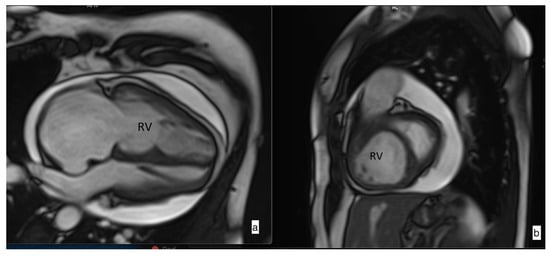

Cardiac MRI Volumetric and Functional Measurements

2.2. Pulmonary Artery Distensibility